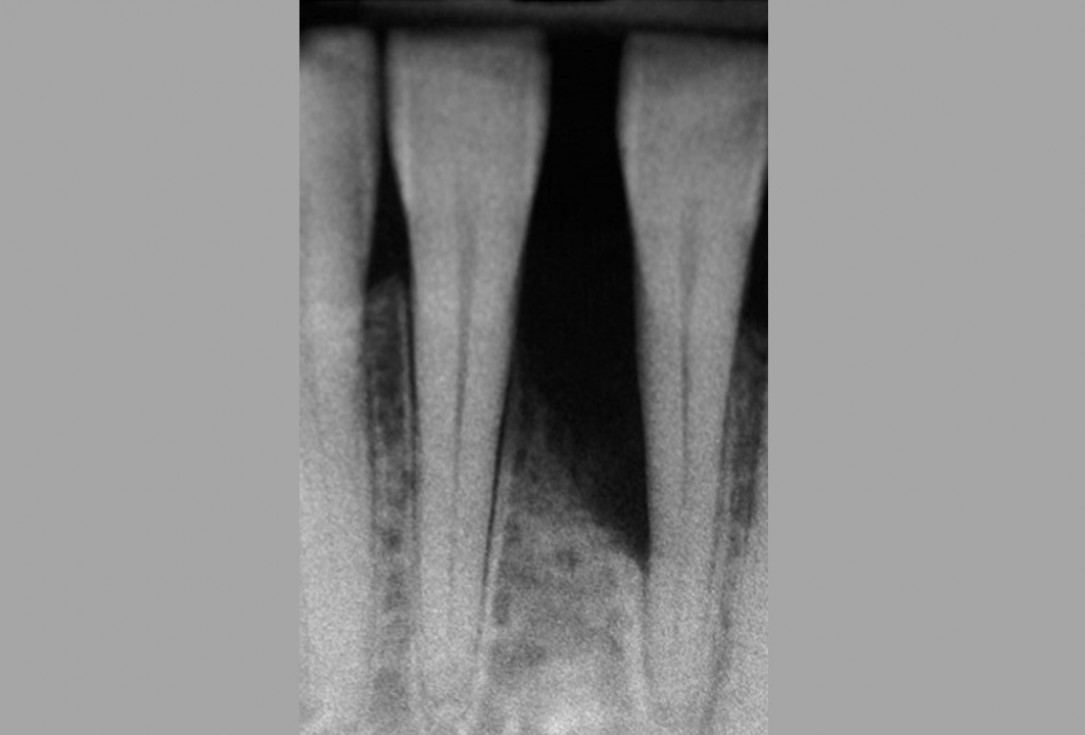

02/13 - Baseline radiograph.

Wide intrabony defect treated with the modified papilla preservation flap in conjunction with Straumann® Emdogain® and autogenous bone - Dr. B. Molnar